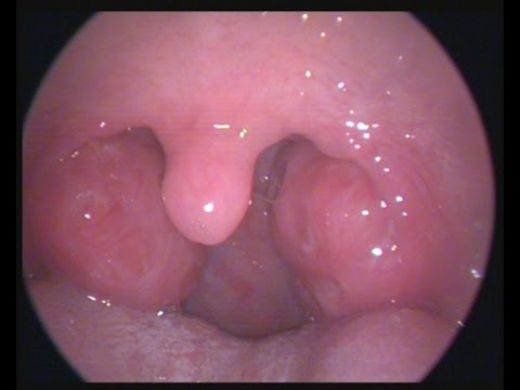

Ameliyat Sonrası Dönem Ameliyat sonrası süreç, hastaların iyileşme sürecinde önemli bir rol oynamaktadır. Bu dönemde dikkat edilmesi gereken hususlar şunlardır:

İyileşme Süreci Bademcik ameliyatından sonraki iyileşme süreci genellikle 1-2 hafta sürer. Bu süre zarfında hastalar, boğazda rahatsızlık, hafif kanama veya enfeksiyon belirtileri yaşayabilir. İyileşme sürecinin sağlıklı bir şekilde geçmesi için:

Sonuç Bademcik ameliyatı, belirli sağlık sorunları için etkili bir tedavi seçeneği sunmaktadır. Ancak, ameliyat öncesi ve sonrası süreçte dikkat edilmesi gereken riskler ve durumlar bulunmaktadır. Hastaların, ameliyat öncesinde doktorlarıyla tüm olası riskler ve beklentiler hakkında açık bir iletişim kurmaları önemlidir. Ameliyat sonrası dönemde ise, doktorun önerilerine uymak ve sağlıklı bir iyileşme süreci geçirmek, başarılı bir sonuç almak açısından kritik öneme sahiptir. |